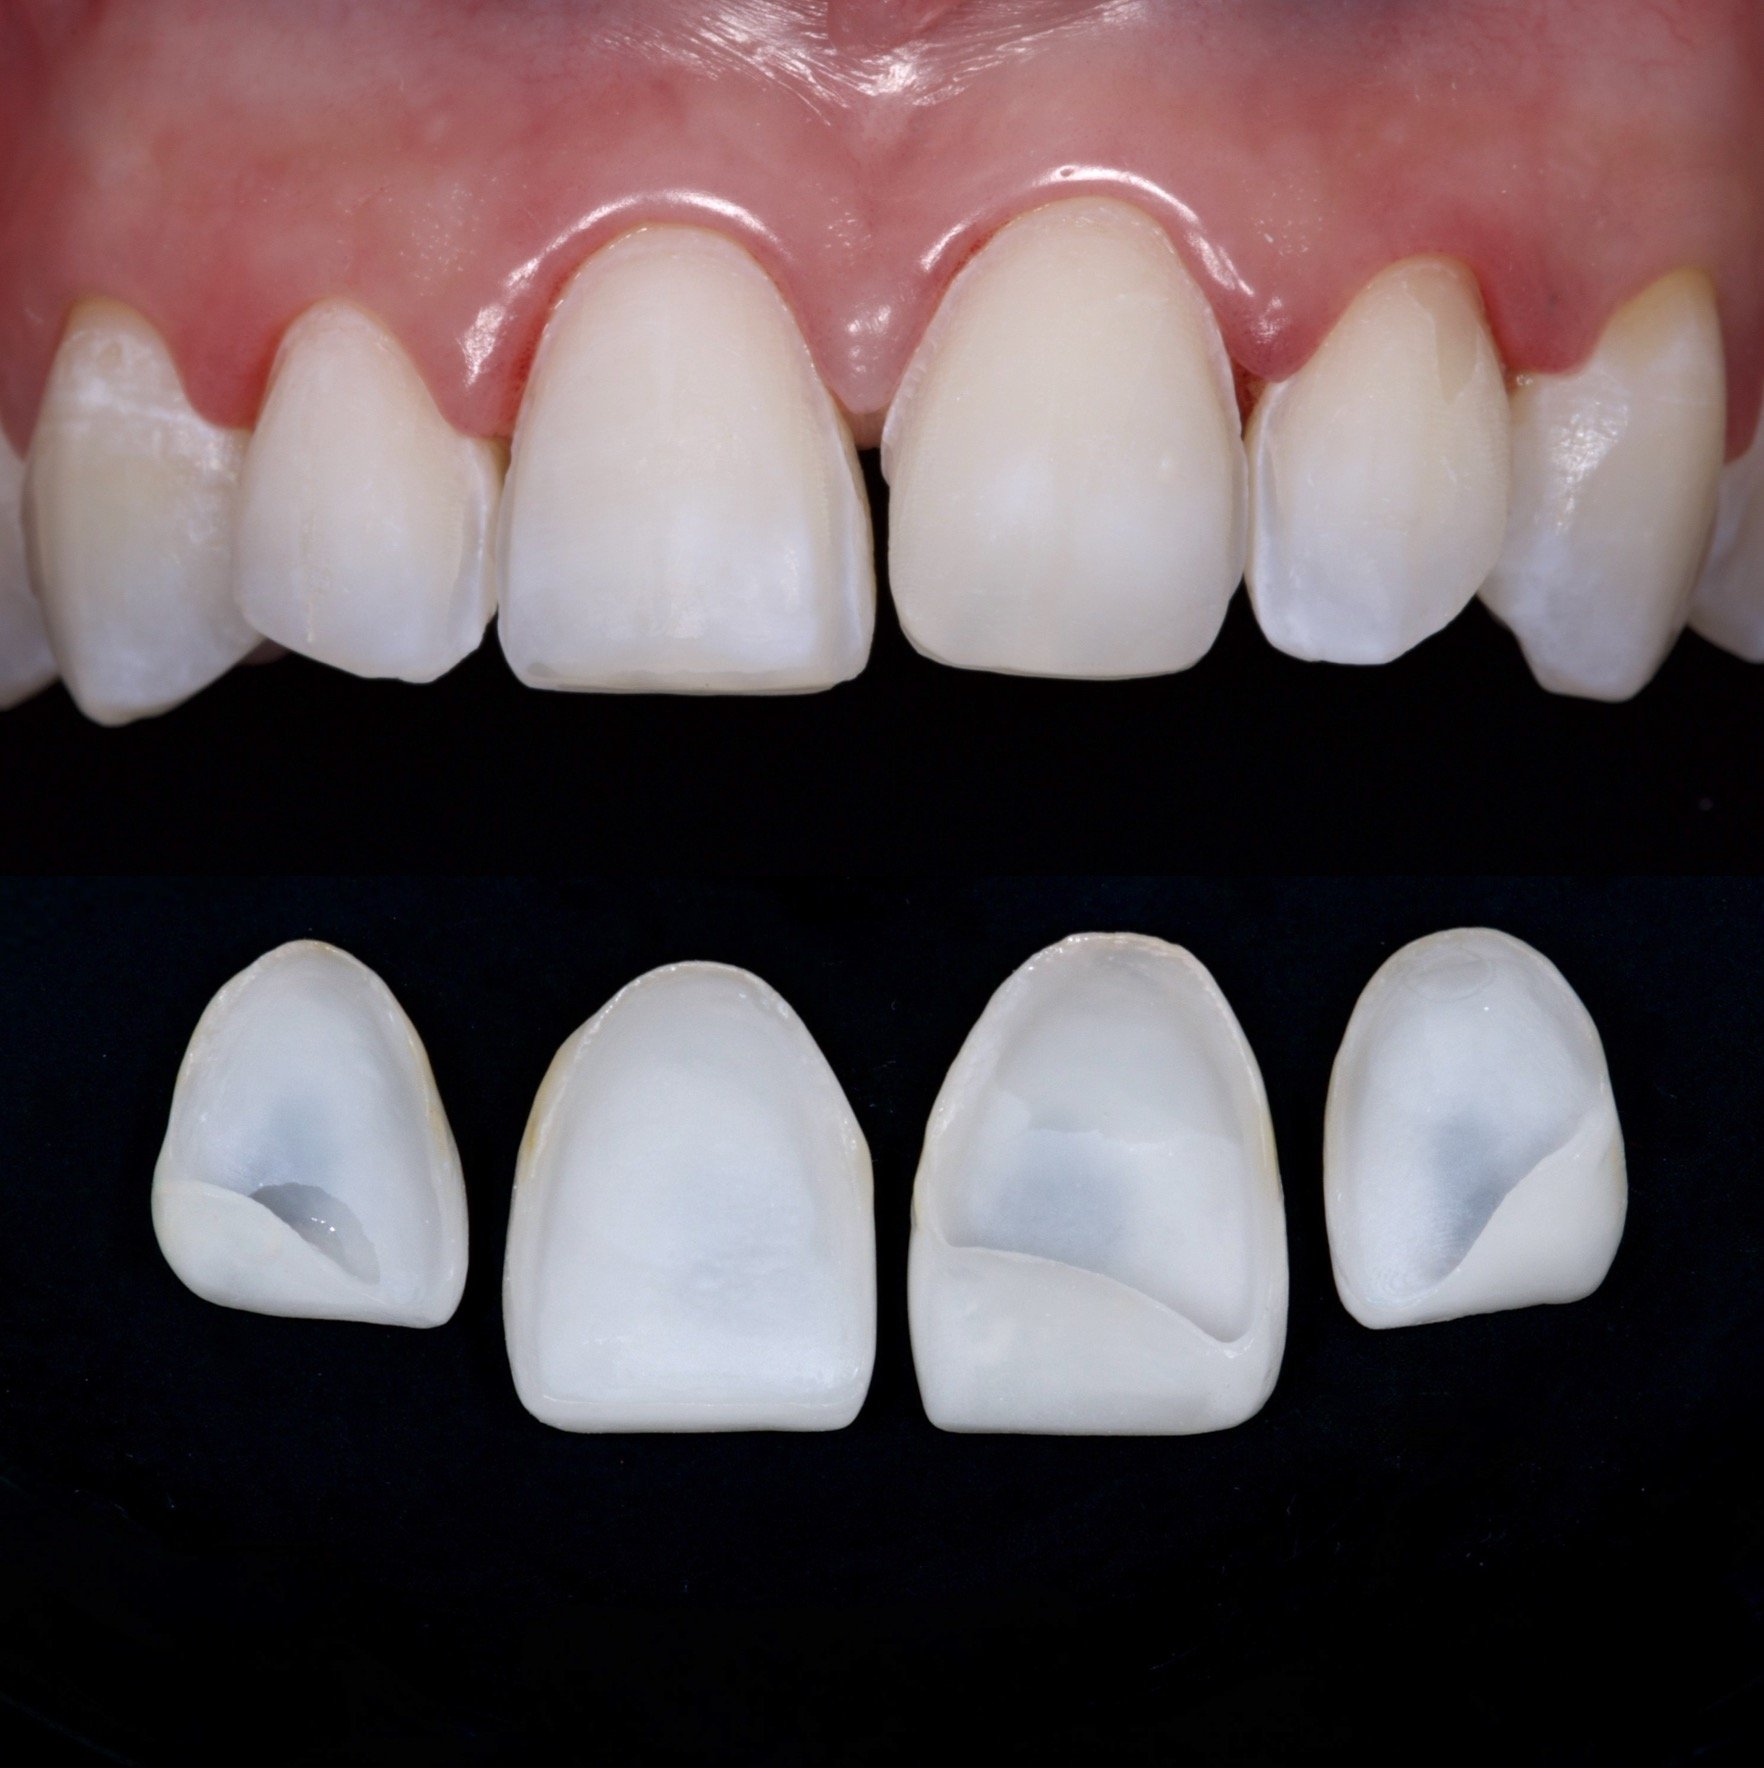

4 Minimal Prep Veneers in Shade 0.5M1

Dr. Heldt, 2025. Newport Beach, California.

Because the patient is not interested in orthodontics, we were able to have the teeth appear straightened with 4 veneers. This is not the doctor’s recommendation by the way. 4 Layered eMax Veneers (#7-10) in Shade 0.5M1. Diagnostic waxup with patient-approved temporaries for shape and shade. Low translucency. No staining.